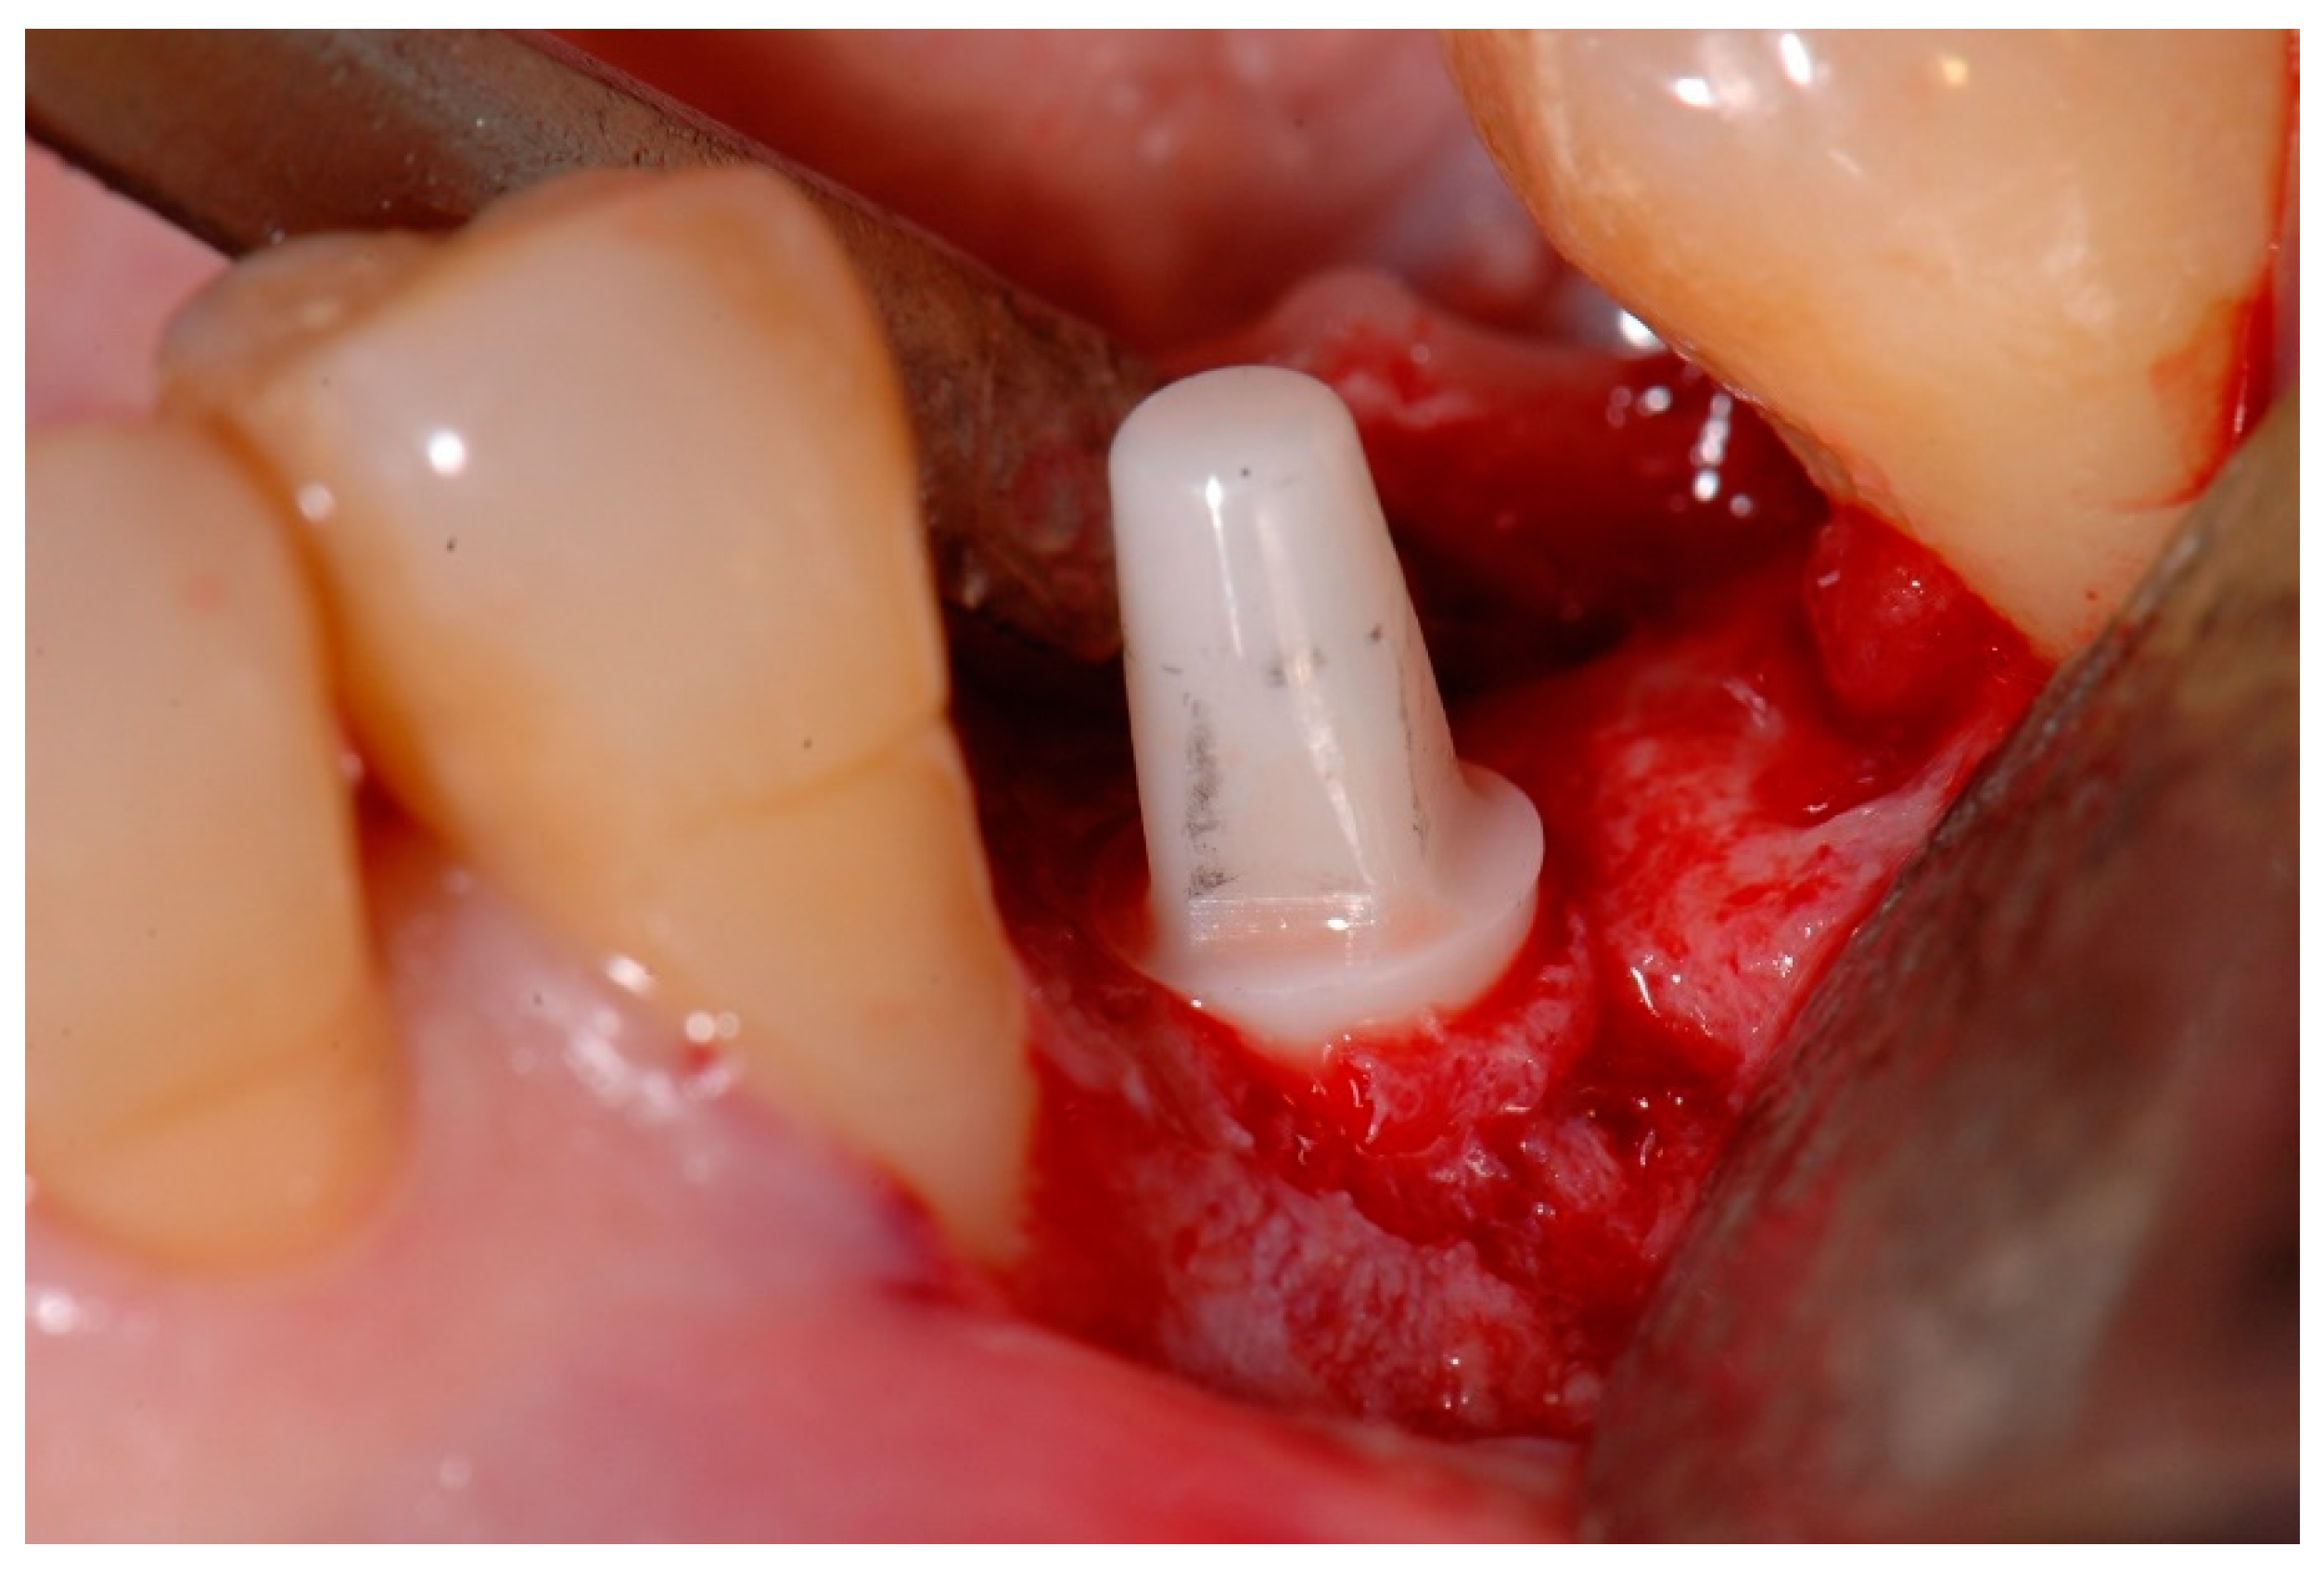

Afterwards, GBR procedures were performed if needed, a plastic abutment protector was placed, and flaps were closed with single sutures to ensure transmucosal implant healing. An intraoral radiograph was taken immediately after surgery (Figure 3). Postoperative medication was then prescribed in the form of amoxicillin 500 mg (or clindamycin 300 mg in patients allergic to penicillin) every 8 h for 7 days, ibuprofen 600 mg every 8 h for four days, and chlorhexidine rinses twice a day for 15 days.

Figure 2. Intraoperative view of a one-piece zirconia implant placed in the mandibular left second premolar position.